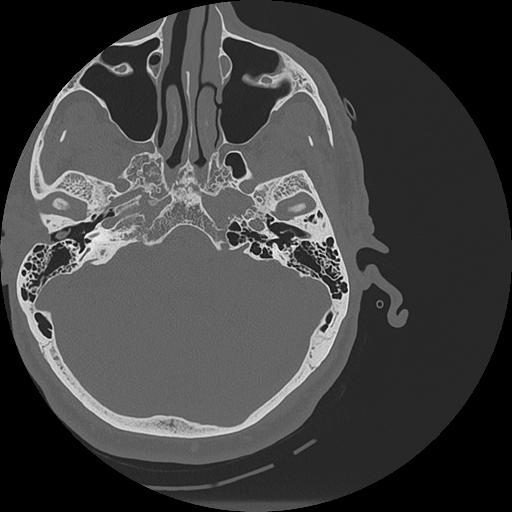

7 HUESO,,Vol,0.5,HUESO,,